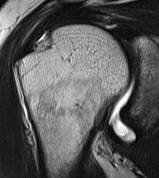

Articular Sided / PASTA (partial articular sided tendon avulsion)